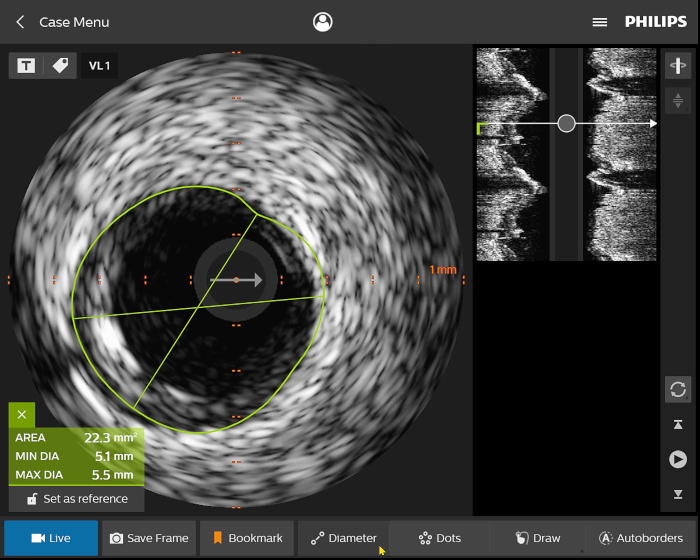

Digitale IVUS- Bildverarbeitung

Abbildung 2

Abbildung 3

Abbildung 4